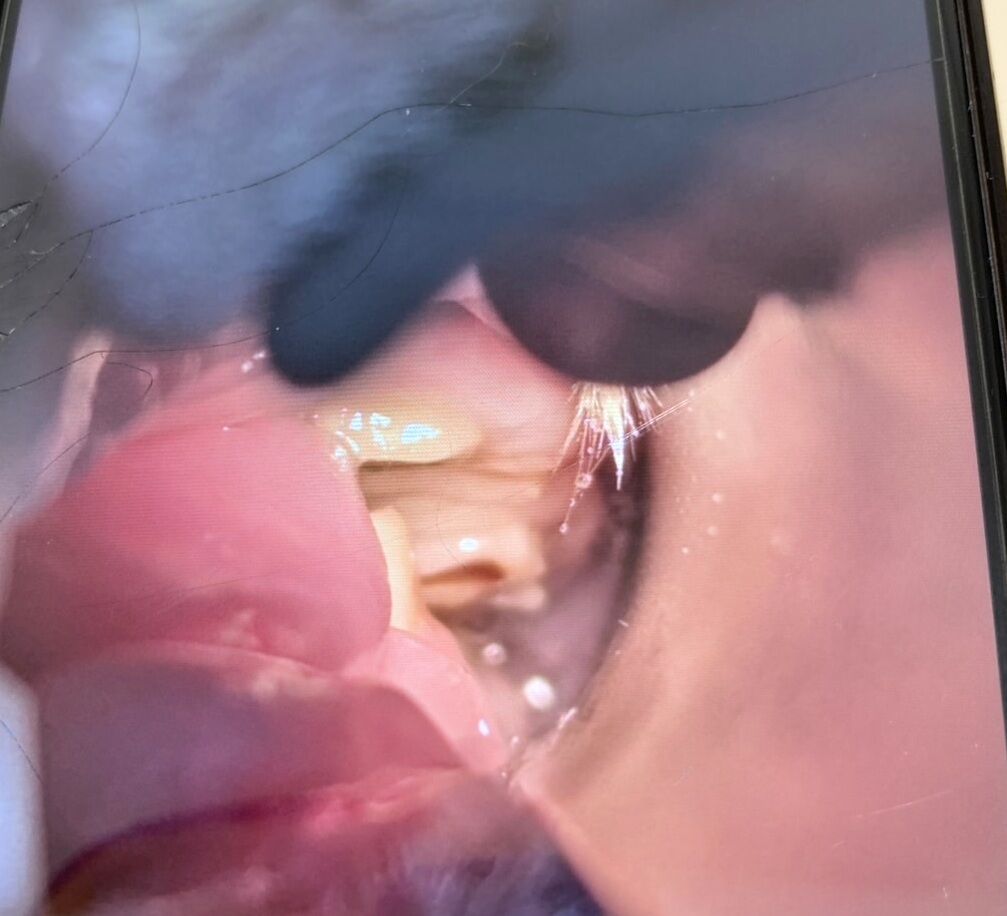

ベルくん【師走っこ】

2024年3月に食欲が落ち、歯が伸びていたのが原因だったため定期的に通院しています。

1/22 右下奥歯が舌の方に尖っていたとのこと。

写真は左の歯で、ガタガタですが、尖って痛そうところは今回ありませんでした。

通院先でベルくんの里親希望のお話があり、交渉中です。

2/26 追記 残念ながらうさぎ以外の動物のお迎えが決まったそうで、白紙になりました。